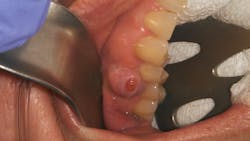

Patient: 50-year-old female

- Raised tissue mass between teeth nos. 4 and 5

- Penicillin allergy and history of type 1 and 2 herpes

- 6 mm pink, raised, firm mass of osseous tissue measuring 12x12 mm

- Lesion not tender to palpation and does not bleed easily when manipulated

“My doctor said I have an infection on one of my top right teeth”